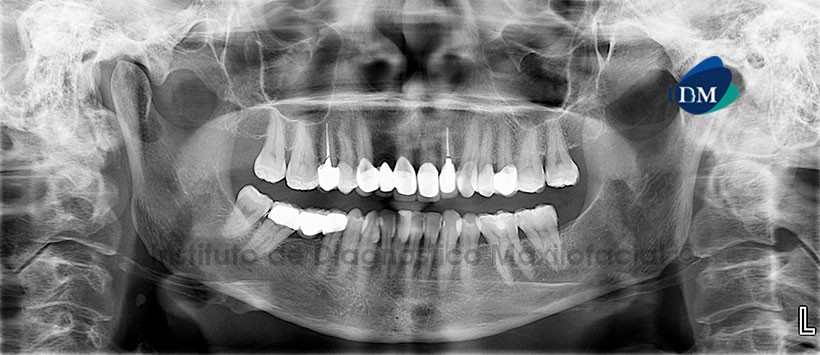

Paciente femenino, 53 años de edad, es referido al Instituto de Diagnóstico Maxilofacial (IDM) para evaluación tomográfica de los rebordes edéntulos con fines de colocar implantes.

A la evaluación de la radiografía panorámica se aprecia una imagen radiopaca de densidad cálcica proyectada sobre la vía aérea a nivel de la cuarta vértebra cervical (C4) y próximo al ángulo mandibular del lado derecho, signos radiográficos compatible con calcificación de tejido blando sugerente de probable ateroma, Además se aprecia zonas edéntulas y mútiples piezas con tratamiento de conducto, restauraciones coronarias y protésicas. (Figura 1).